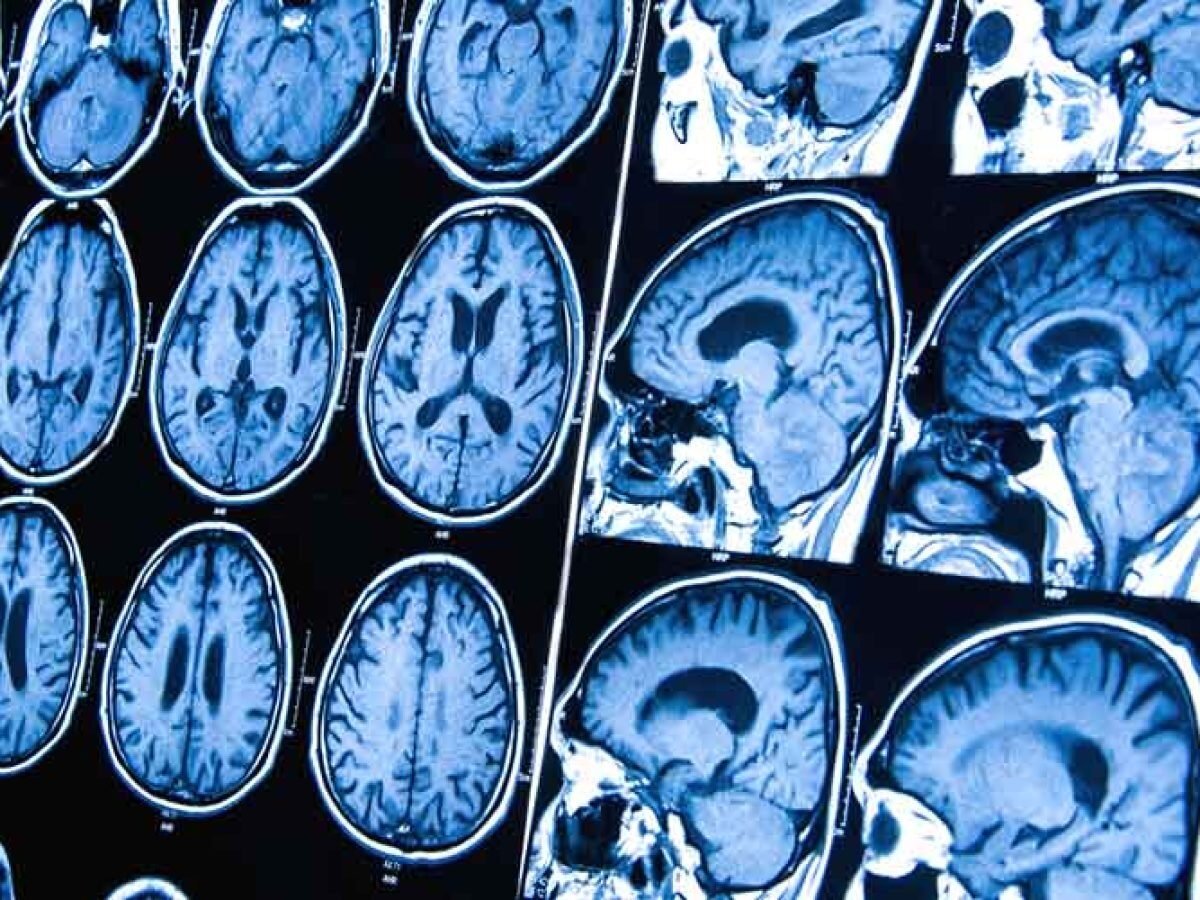

Detectar un tumor cerebral de forma temprana es clave para mejorar el pronóstico. El Hospital Houston Methodist utiliza tecnología avanzada y combina métodos clínicos e imágenes para un diagnóstico exacto, tales como:

Resonancia magnética (MRI): Técnica no invasiva que emplea campos magnéticos y ondas de radio para obtener imágenes detalladas del cerebro.